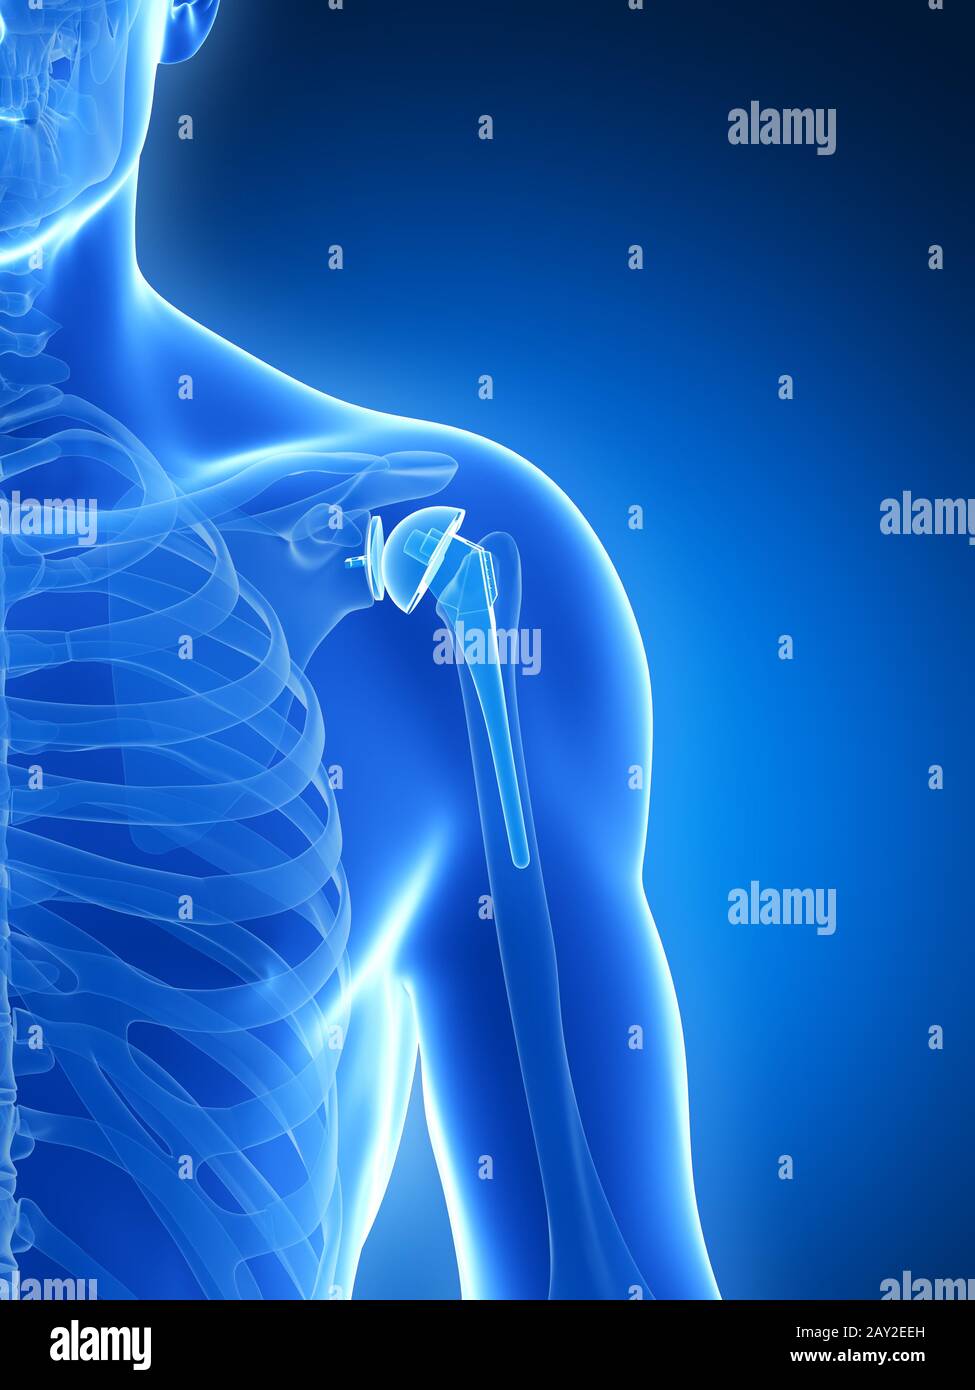

Reversible Shoulder Replacement. Shoulder joint replacement, endoprosthetics. Osteoarthrosis of Shoulder Replacement Surgery Video Animation This animated video demonstrates an anatomic shoulder replacement for the treatment of shoulder arthritis. #shoulderreplacement #osteoarthritis #rheumatoidarthritismedical animation transcript: Watch a medical animation of reverse shoulder replacement surgery, a procedure for patients with rotator cuff tears. Understand.com® is excited to announce the latest improvement to our orthopedic library with the release of the updated total shoulder replacement animation. Learn about. Shoulder Replacement Surgery Video Animation.